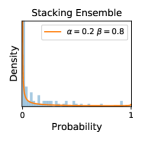

5.1 Distribution of Uncertainty Scores

Distribution of Uncertainty Scores Across Different Severity Levels As explained in Section 3, each uncertainty metric essentially defines an order/ranking among the data points. We conducted an analysis to better understand what data will be assigned high uncertainty under a particular uncertainty metric . Picking out the highest ranked data points (), we calculated the ratio of data points from each SL. Figure 4 summarizes the results as box plots for the Kaggle-DR and the Messidor-2 datasets; additional detailed statistics can be found in Table S.1 in the supplementary materials. From the plot and table, SL1 & SL2 examples account for a higher proportion among the top-ranked uncertain examples across the three ensemble methods. This finding matches our intuition that incipient disease examples (SL1 & SL2) are more likely to be considered uncertain by ensemble methods due to their ambiguity.

Comparing the three ensemble methods in Figure 4, the stacking ensemble method has the highest ratios of SL1 & SL2 data among the high-uncertainty examples it identified under both mean and var. TTA showed slightly better performance than MC-dropout but still falls behind the stacking ensemble method. Considering the fact that SL0 examples accounted for the majority of the dataset, the stacking ensemble method was much more precise (specific) in selecting truly ambiguous data points that were difficult to classify. From Figure 3, we can also see that the stacking ensemble method greatly outperformed the other two methods in finding false negatives under both mean and var uncertainty metrics.

In contrast, the MC-dropout method showed the worst overall performance among the three, as it can be seen from the high ratios of SL0 examples among the uncertain negatives in Figure 4. The histograms in Figure 2 provides another perspective to look into the phenomenon, where a decent proportion of MC-dropout model’s predictions on SL0 inputs entailed low confidence (far from 0 or 1), which from another angle explained why MC-dropout was less specific in terms of lower FNP; many no-DR inputs (i.e. SL0) were erroneously assigned high uncertainty by MC-dropout models.

It is still an open question why the evaluated MC-dropout networks signaled relatively high uncertainty on SL0 & SL3 & SL4 data that are less likely to be ambiguous. We conjecture that much of the “uncertainty” indicated by disagreement among test-time dropout samples actually reflects the stochastic nature of dropout networks rather than the real decision uncertainty associated with the data. It is worth noting that the MC-dropout model we evaluated was not weak per se; they all achieved above Area Under Curve (AUC) scores on test sets. The weakness of individual test-time samples (which explains their low-confidence predictions on SL0 & SL3 & SL4) might have been hidden when they are aggregated into an ensemble—a well-known advantage of ensemble learning. Our results suggested that the uncertainty information given by implicit ensemble methods such as MC-dropout and TTA might not be as reliable as that from explicit ensemble approaches (e.g., stacking ensembles). Similar findings on MC-dropout can be found in some previous papers [1].